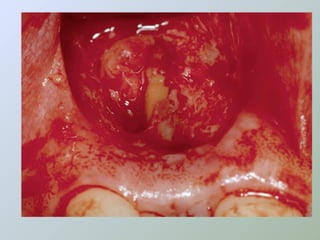

Caso 1

Caso 2